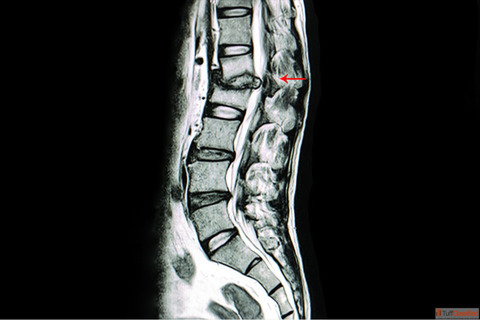

Get expert Tuberculosis Spine Surgery in Vizag from Dr. B. Leela Prasad, a trusted spine surgeon known for advanced diagnosis and minimally invasive corrective procedures. His treatment approach focuses on removing infected tissue, stabilizing the spine, and preserving maximum mobility while ensuring faster healing and reduced complications.

If you are experiencing spinal pain, weakness, or neurological symptoms due to TB of the spine, Dr. Leela Prasad provides precise, evidence-based care to restore stability and prevent further deformity. Book your consultation today for safe and effective TB spine treatment in Vizag.